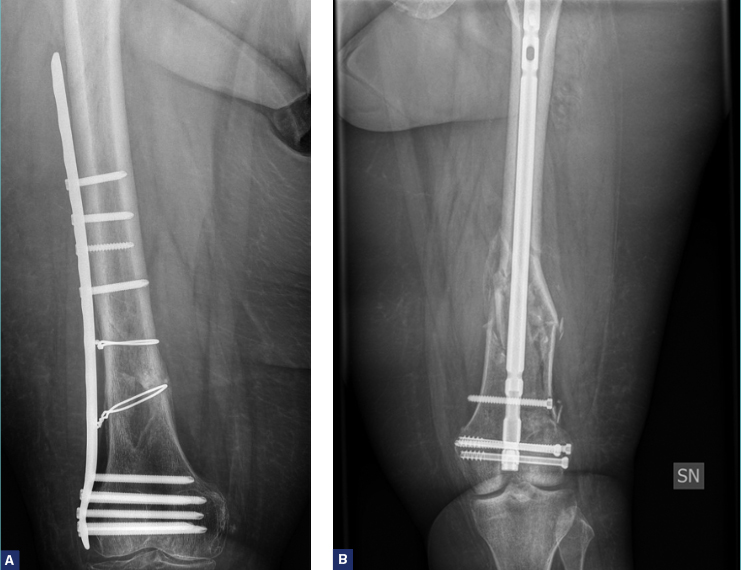

L’utilizzo delle placche ha visto il progressivo abbandono delle Lame-Placca a stabilità fissa ovvero placche angolate di 95 gradi che forniscono una fissazione stabile controllando l’allineamento in 3 piani, e di difficile applicazione, per far spazio alle placche DCS, e sempre più recentemente alle placche LISS (“Less Invasive Stabilization System”). Si tratta di placche modellate anatomicamente preconformate che offrono la versatilità aggiuntiva di opzioni di fori distali multipli per le viti, combinate con la possibilità di comprimere i frammenti e conferire stabilità angolare. L’applicazione inoltre si può ottenere con una tecnica meno invasiva, con tecnica a scivolamento (MIPO). Le guide di allineamento infatti consentono il posizionamento percutaneo delle viti prossimali 9 (Fig 2. A-B).

La fissazione con un chiodo endomidollare è generalmente usata per fratture extra-articolari e fratture intra-articolari semplici o minimamente comminute. Questo impianto consente di fissare la frattura con un ridotto insulto dei tessuti molli e dell’apporto arterioso endostale provvedendo e una distribuzione dei carichi ottimale al fine di permettere molto spesso un carico precoce. Le complicazioni possono derivare da un disallineamento della frattura a causa di una riduzione insufficiente della riduzione della frattura, di un punto di partenza inadeguato o di un alesaggio eccentrico.